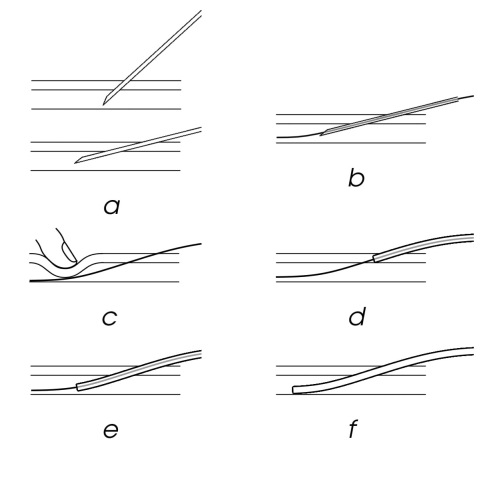

II-B Seldinger Technique

The Seldinger technique [19] (Fig. 2) is a surgical method for placing a catheter into a vessel. It was developed in the 1950s, replacing previous methods that involved either exposing the artery surgically using a blunt cannula or large-bore needles that could carry a catheter inside them. While previous techniques often inflicted damage to the vessel wall, Seldinger technique avoids these complications by inserting a needle parallel to the skin directly into the vessel (Fig. 2a) and tilted to be more parallel to the skin. Then, a flexible guide wire is inserted through the needle (Fig. 2b). The needle is removed (Fig. 2c,d) and the catheter is slid over the guide wire into the artery (Fig. 2e,f). This method has been further augmented with the use of sagital and transverse ultrasound to guide the needle insertion, with better outcomes for the patient[27, 23]. This method is not foolproof, however, and can still cause complications when performed by professionals[16]. Although more advanced techniques such as ECMO and REBOA require serial tissue dilations and complex insertions at the access point, both these techniques or even the most basic IV placement depend on this primary coordinated effort to assure functional success.